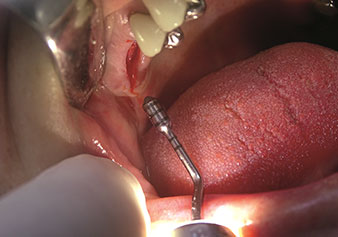

Un’applicazione che viene spesso sottovalutata è l’estrazione atraumatica di radici di denti o frammenti di radici nell’ambito della gestione alveolare. I periotomi sottili, che sono attualmente disponibili in due versioni (EX1 ed EX2 di W&H), possono essere, inoltre, utilizzati per rimuovere con facilità denti che hanno precedentemente subito uno specifico trattamento endodontico o con radici anchilosate. Ne consegue l’estrazione di alveoli in cui i tessuti duro e molle sono entrambi completamente intatti in quanto è generalmente possibile evitare la riflessione.

Ciò pone le basi ottimali per un trattamento con impianto immediato o successivo (Figure 1 e 2 inserite grazie alla gentile concessione del Dott. Torsten Conrad, Bingen a. Rhein).

Periotomo sottile (strumento EX1)

Fig. 1: Periotomo sottile (strumento EX1).

Foto: © Dott. Torsten Conrad (Bingen a. Rhein)